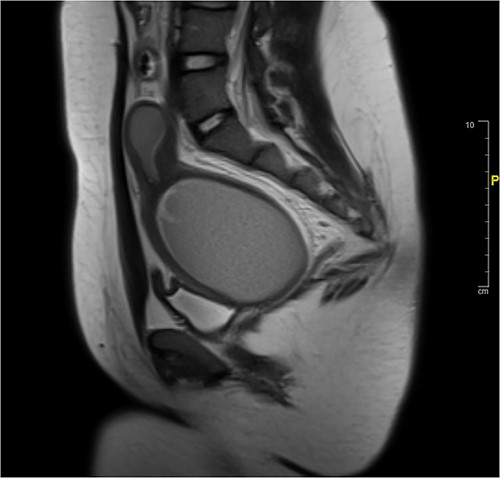

Attempt was made to perform US-guided drainage in IR using largest bore drain (12F) but the HMC had organized into a large clot and was too thick for drainage. Four mg of TPA was then injected into the HMC to allow breakdown of the clot, after which 300 ml of blood was successfully drained (Fig. 2).

Pre-vaginoplasty MRI- Image was taken after IR drainage and suppression to allow distension pre-vaginoplasty.